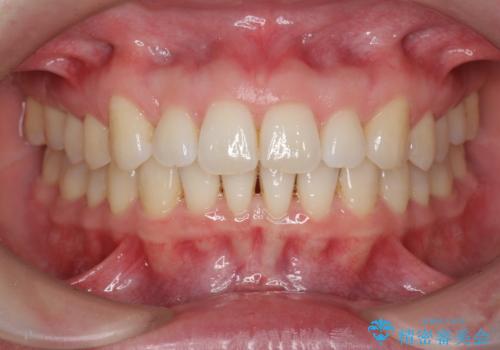

- 前歯の突出感、出っ歯の治療を希望され来院されました。

インビザラインを用いた治療計画を立て、しっかりと出っ歯を治すためにマイクロインプラントを併用します。

マイクロインプラントを併用することでしっかりとマウスピース全体を後方へ引き、前歯の突出感を改善することができました。